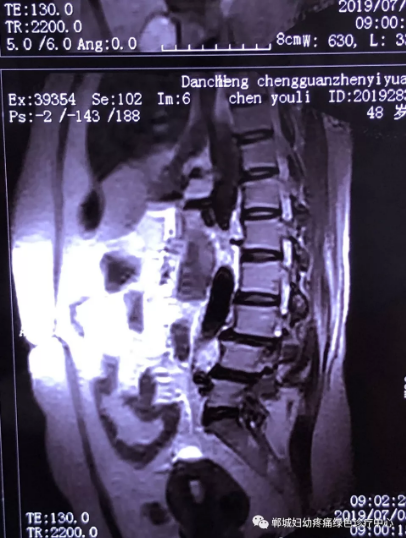

2年前,雙樓鄉(xiāng)的陳女士不小心摔了一跤后出現(xiàn)腰痛,當時到藥店買了膏藥來貼,疼痛減輕了一些,但是從此以后反反復(fù)復(fù)出現(xiàn)腰痛。到處進行治療,不見好轉(zhuǎn),最近腰痛加重了,痛得受不了,出現(xiàn)行走后甚至持續(xù)的雙下肢后側(cè)或后外側(cè)放射性的疼痛麻木、間歇性跛行等癥狀。陳女士趕忙去醫(yī)院治療,做了磁共振檢查后確診為腰椎滑脫、腰椎反弓。醫(yī)生都告訴她需要手術(shù)治療。隨后她又帶著片子咨詢了好幾家醫(yī)院,結(jié)果都是一樣,她已經(jīng)做好了手術(shù)的打算。

治療前

不經(jīng)意間聽到有人說醫(yī)院疼痛科可以不吃藥不打針,用無痛苦、無創(chuàng)傷的方法治療腰痛。陳女士就抱著試試看的心理來到了鄲城縣婦幼保健院疼痛科,疼痛科時慶祥主任詳細了解病情,結(jié)合腰椎磁共振及體征后告訴陳女士她不用手術(shù),通過腰椎脊柱定位周期減壓牽引系統(tǒng)(外星艙)也能解決腰痛、腰椎滑脫、腰椎反弓這些問題。陳女士未曾想到經(jīng)過十五天的治療后腰部及下肢放射性疼痛癥狀基本消失。陳女士感到十分激動與感謝,就在當?shù)匦l(wèi)生院做了一個腰椎正側(cè)位x片和之前的片子作對比,發(fā)現(xiàn)腰椎滑脫明顯改善。她說道:感謝鄲城縣婦幼保健院疼痛科的所有醫(yī)護人員、感謝外星艙脊柱減壓治好了我的腰痛,也感謝告訴我來這里的人,她的一句話,讓我省了好幾萬元的手術(shù)費!